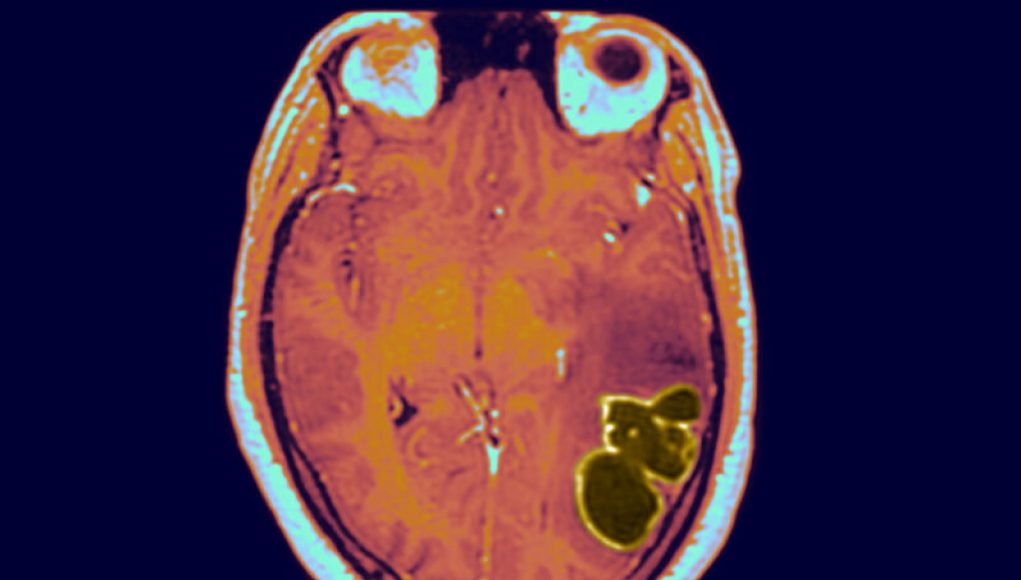

Brain abscesses can be caused by bacteria, viruses, or fungi entering the brain and forming an encapsulated area around the germs and pus. Streptococcus bacteria seem to be the main culprit in the recent rise. The infections can start in several ways, including from an infected head wound, meningitis, and congenital heart disease, but also more common conditions, such as sinus and ear infections. If left untreated, the pockets of pus in and around the brain can lead to rapid deterioration and permanent brain damage, causing severe neurological complications, such as seizures and difficulty with movement, speech, and cognition.

A brain abscess is a pocket of infection that forms within the brain due to bacteria, fungi, or rarely, parasites. A recent study conducted by the Center for Disease Control and Prevention (CDC) suggests that the number of of children in the US diagnosed with a brain abscess has tripled since the beginning of the pandemic. During the first half of 2020, less than 1.2 cases were reported per 100,000 children. In contrast, the new study revealed that during the second half of 2020, more than 3.4 cases were reported per 100,000 children.